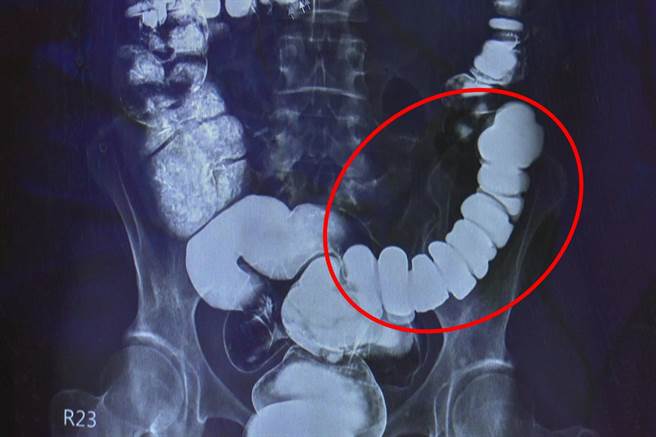

大腸直腸外科主任邱建銘從大腸攝影檢查發現,江小姐腸子繃得非常緊。這類典型情緒影響腸道病例,臨床不算少,但仍驚訝「沒看過把自己腸子逼得這麼緊。」邱建銘問診得知病人易焦慮個性以及澳洲生活與求診的坎坷,才確認需要手術解決。

邱建銘保留江小姐一小段升結腸,以腹腔鏡切除大部份大腸,再吻合升結腸與乙狀結腸,減少術後嚴重腹瀉或夜間滲便,也減緩嚴重便秘。家人看見切除的腸子緊縮成一團,才理解她多年來的痛苦,並非無病呻吟。